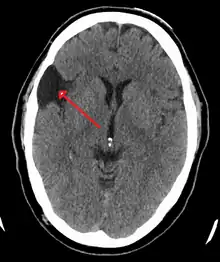

| Arachnoid cyst | |

Diagnosis is principally by MRI. Frequently, arachnoid cysts are incidental findings on MRI scans performed for other clinical reasons. In practice, diagnosis of symptomatic arachnoid cysts requires symptoms to be present, and many with the disorder never develop symptoms.